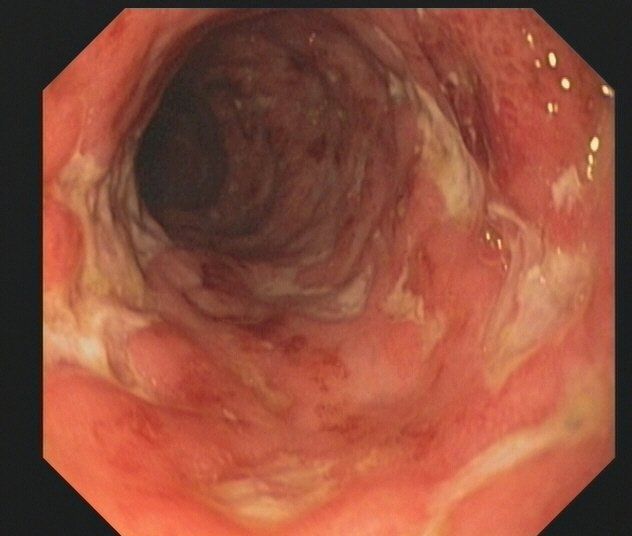

• Spezialsprechstunde für Patienten mit chronisch entzündlichen Darmerkrankungen Morbus Crohn und Colitis ulcerosa

• Barrett-Ösophagus

Zu den Untersuchungen gehört das Austasten des Mastdarms mit dem Finger und der fäkale Okkultbluttest, die ab dem 50. Lebensjahr empfohlen werden. Diese Maßnahmen ersetzen aber nicht die vollständige Darmspiegelung, mit der der gesamte Dickdarm inspiziert wird. So kann Darmkrebs frühzeitig erkannt werden, die Prognose wird verbessert. Durch Abtragung von Polypen, die Krebsvorstufen darstellen, wird die Entstehung von Darmkrebs verhindert. Die Entfernung von Polypen ist im Rahmen der Darmspiegelung meist problemlos und mit nur geringem Risiko möglich. Große Untersuchungen haben gezeigt, dass die Vorsorgekoloskopie sehr sicher ist.

Bei erblicher Prädisposition (Verwandte ersten Grades von Darmkrebs-Patienten) wird die Darmspiegelung früher durchgeführt. Patienten mit Polyposis-Syndromen (familiäre adenomatöse Polyposis, Peutz Jeghers Syndrom etc.), nicht polypösem Kolonkarzinom-Syndrom (HNPCC) und chronisch-entzündlichen Darmerkrankungen (vor allem Colitis ulcerosa) haben ein stark erhöhtes Darmkrebsrisiko und müssen sorgfältig endoskopisch überwacht werden. Die Leitlinien der Deutschen Gesellschaft für Verdauungs- und Stoffwechselerkrankungen (www.DGVS.de) geben die Untersuchungsintervalle vor.